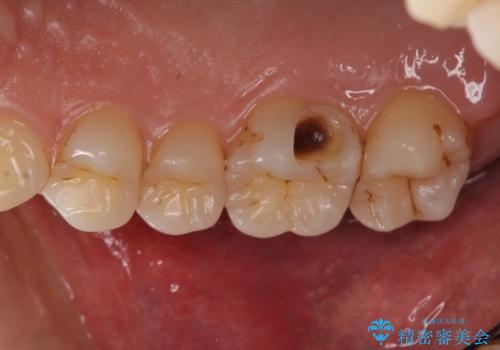

前歯のブリッジの見栄えが悪い→見えないところからしっかりとやり直しを

一見きれいにはいっているセラミックも、はずして中の状態をみるとひどいことが多い。これは、中の土台の状態や処理のクオリティは、短期的には問題を起こしづらく、患者さんには見えない部分だからです。